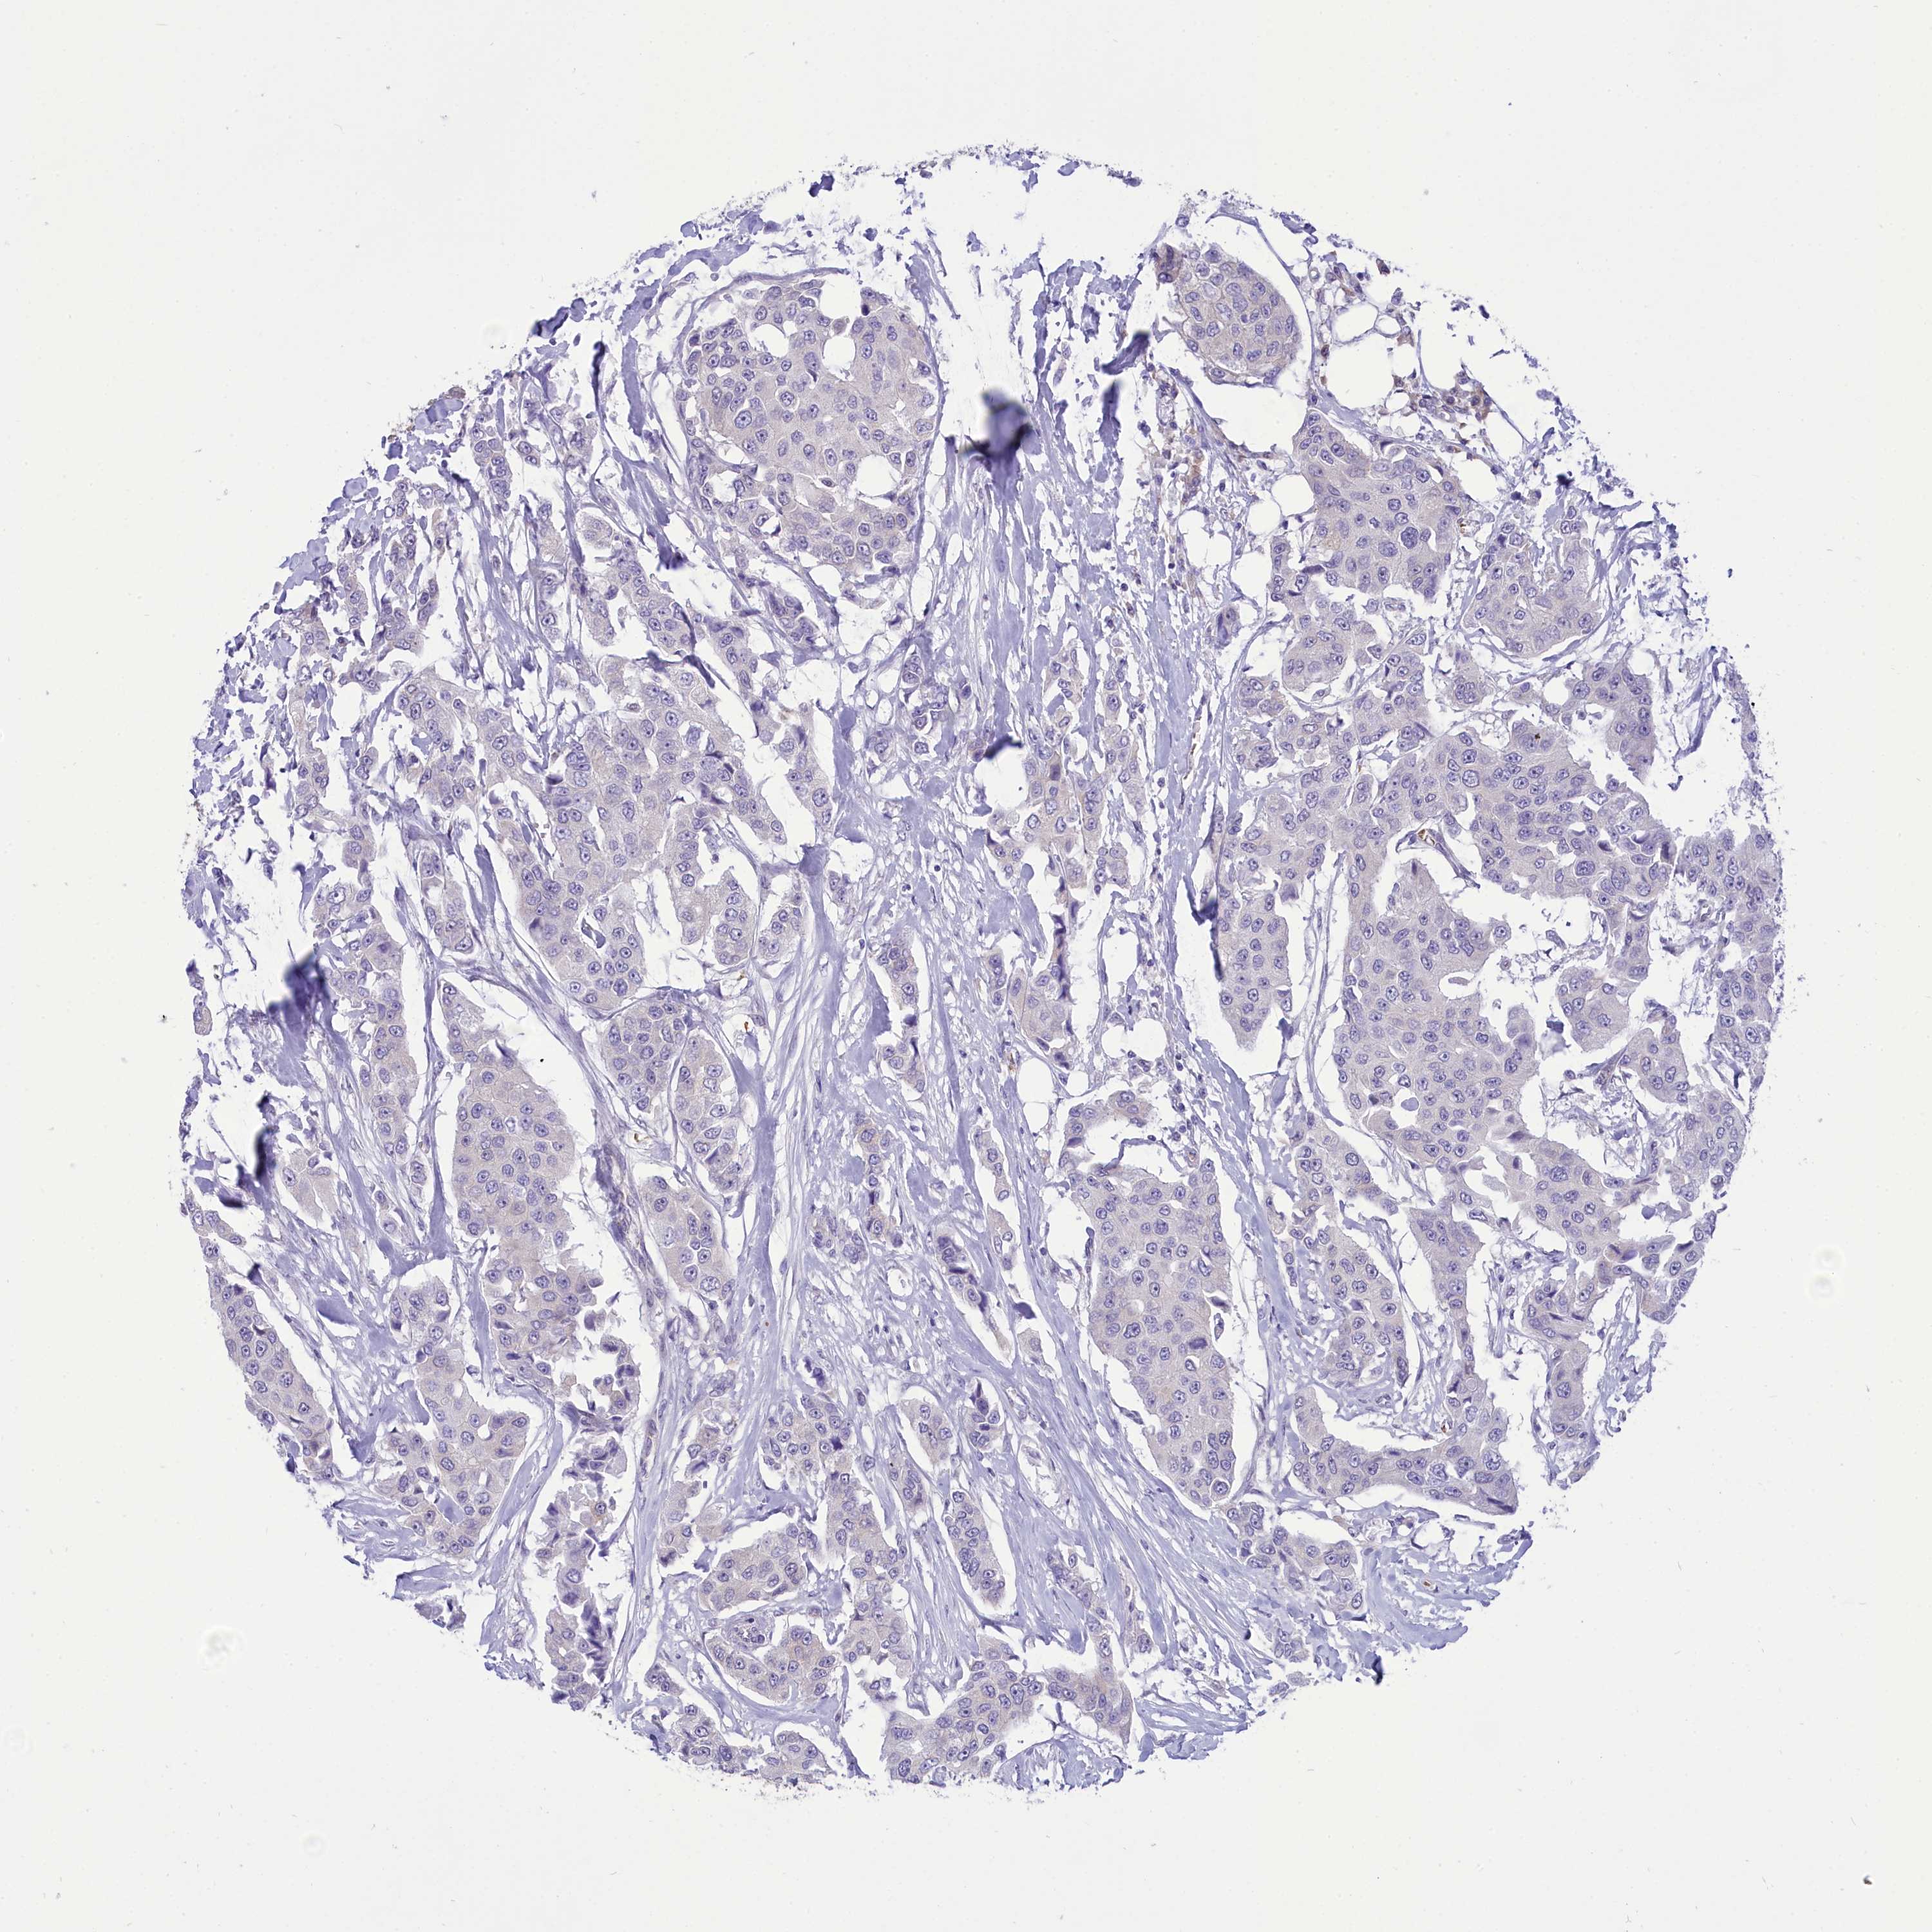

BRCA TCGA BRCA VALIDATION PROTEIN EXPRESSION

ANTIBODIES

AND

VALIDATION